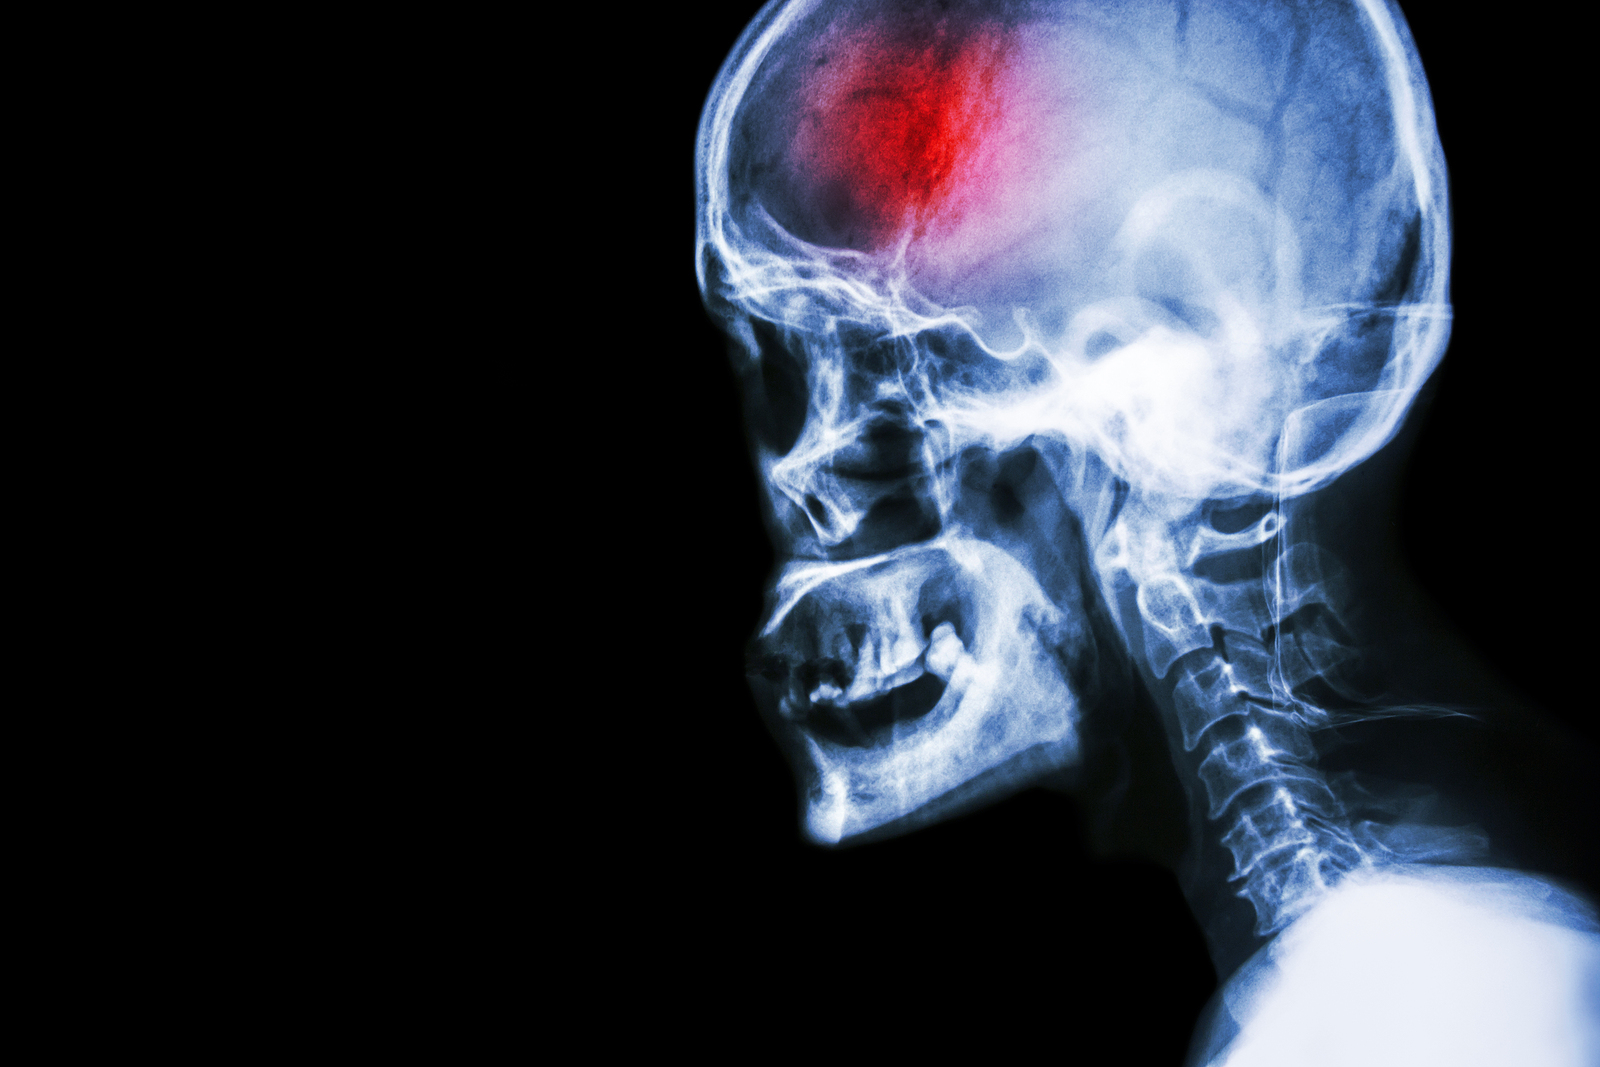

What is a stroke?

A stroke (previously known as a cerebrovascular accident) when there is a decreased flow of blood to the brain from either a blockage in the blood vessels that supply the brain (ischemic stroke), or a bleed from the blood vessels that supply the brain (hemorrhagic stroke). When the blood flow to the brain is blocked it prevents the brain from getting the needed oxygen and nutrients to function. Without oxygen the brain cells can be permanently damaged or die and the physical and mental functions related to that area of the brain will be affected. A stroke is a medical emergency and rapid treatment is crucial to decreasing the damage caused by a stroke.

Types of strokes

There are three types of strokes:

- Ischemic stroke: a stroke that is caused by a blockage (clot) that disturbs the blood flow to the brain.

- Hemorrhagic stroke: a stroke that is caused by a bleed that disturbs the blood flow to the brain and puts pressure on the surrounding tissue.

- Transient ischemic attack: often referred to as a “mini-stroke” or TIA, where the blood flow to the brain is temporarily disturbed and as a result causes temporary signs and symptoms of a stroke that resolve quickly .

What happens with a stroke?

When any type of stroke occurs and the blood flow to the brain is compromised, all the functions which that part of the brain controls are subsequently disturbed. The brain on one side of the head controls the movement functions and sensation on the opposite side of the body. This means that if you have a stroke on the left side of the brain, the right side of the body will be affected. If the stroke is on the right side of the brain, the left side of the body will be affected.

Every stroke is unique depending on exactly which area of the brain has been affected. The bigger the bleed or blockage and the longer that the stroke goes without treatment (to stop the bleed or unblock the blockage), the more severe the impairments and the greater number of abilities that will be affected. It is worth reiterating that time is of the essence when a stroke first occurs; early treatment can immensely improve outcomes.